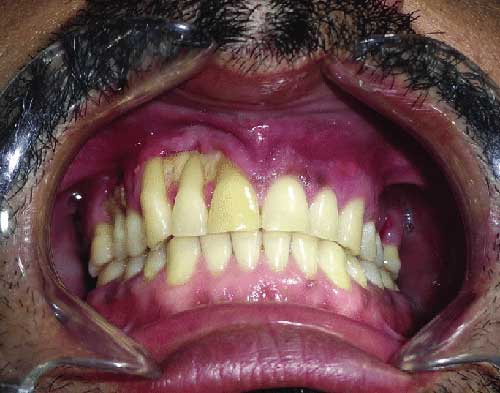

This fungal infection first occurs in the sinuses after corona recovery. And begins to damage upper teeth, gums and the bones of upper jaw.

- If we talk about the symptoms of mucormycosis, in this disease the patient initially has toothache (tooth pain), jaw pain and swelling in the upper jaw, swelling in the side of the nose. Symptoms include bleeding from the gums and loosening of the teeth.

- Proper cleaning of gums and teeth is mandatory. If you find rotten, decayed or infected teeth, visit your dentist. (If you are in Rajkot, you can visit our Sanjivani dental clinic.)